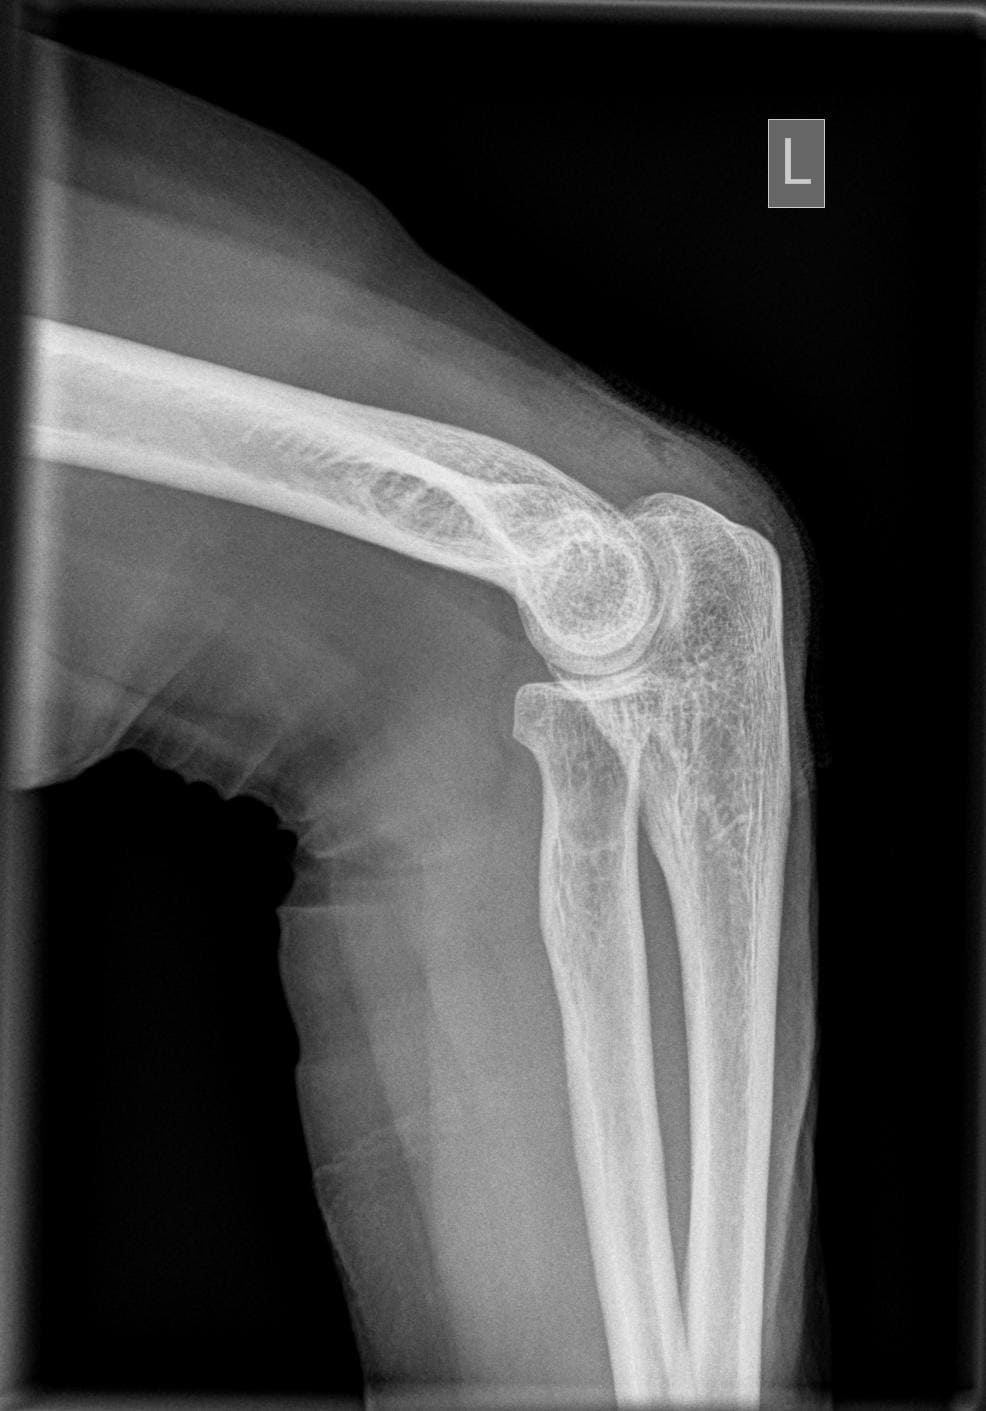

Ellenbogen seitlich

Ellenbogenseit_zum_Unterarm.jpg

Fehler

Der distale Oberarmteil ist schräg projiziert, d.h. die beiden Gelenkrollen überdecken sich nicht. Hier gibt es eine Doppelkontur der Gelenkrollen in Richtung Handgelenk hin. Ursache hier ist die Schrägprojektion, da Unterarm nicht unterpolstert wurde.

Abhilfe

15°-Keil oder Handgelenk der Gegenhand unter den betroffene Unterarm/Handgelenk legen.